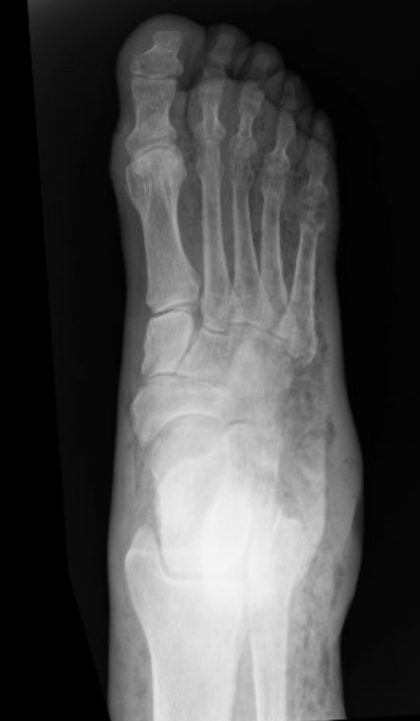

This is a case of necrotizing fasciitis as well. Note the subcutaneous air along the first through fifth metatarsals.

Below is a case of extensive right lower extremity necrotizing fascitis with diffuse subcutaneous emphysema.

Right foot: